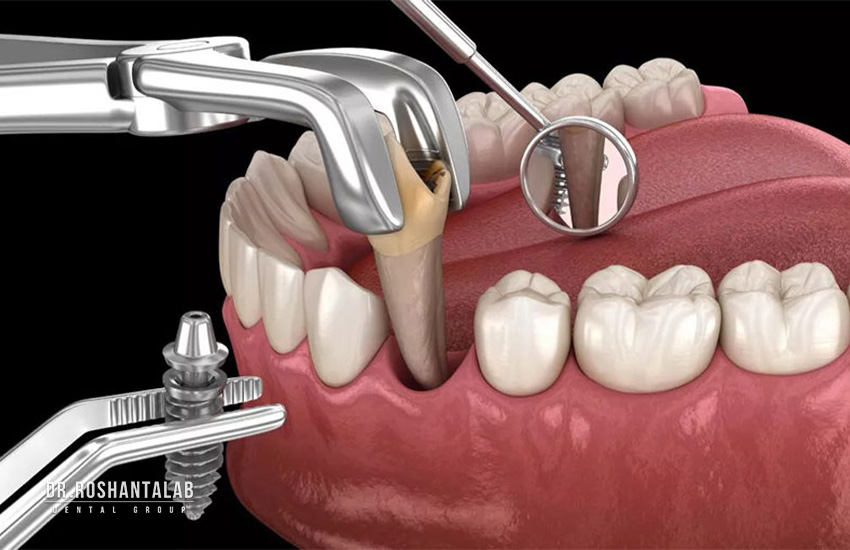

مرحله دوم: زمان مورد نیاز کشیدن دندان و آمادهسازی بستر (در صورت نیاز)

زمان مورد نیاز: 1 جلسه (اما زمان انتظار برای التیام: 1 تا 3 ماه) اگر دندان آسیبدیده هنوز در دهان شما باشد، باید کشیده شود. کشیدن دندان باید به روش “آتروماتیک” (Atraumatic) انجام شود؛ یعنی دندان بدون آسیب رساندن به دیوارههای استخوانی اطراف خارج گردد. اگر دندان عفونت شدیدی نداشته باشد، گاهی میتوان ایمپلنت را در همان جلسه کاشت (ایمپلنت فوری). اما اگر عفونت وسیع باشد، دندانپزشک دندان را میکشد، محل را شستشو میدهد و از شما میخواهد حدود 1 تا 3 ماه صبر کنید تا حفره دندان با استخوان طبیعی شما پر شود و عفونت کاملاً از بین برود.

- کاشت فوری (Immediate Placement): ایمپلنت در همان روز کشیدن دندان کاشته میشود. (برای دندانهای تکریشه جلویی با استخوان سالم).

- کاشت با تاخیر اولیه (Early Placement): دندان کشیده میشود و حدود ۴ تا ۸ هفته (۱ تا ۲ ماه) صبر میکنیم تا بافت نرم لثه روی حفره را بپوشاند، سپس جراحی کاشت انجام میشود.

- کاشت تاخیری (Delayed Placement): اگر دندان عفونت شدید داشته باشد یا استخوان به شدت تخریب شده باشد، دندان کشیده شده و حفره با مواد پیوندی پر میشود. بیمار باید بین ۳ تا ۶ ماه صبر کند تا استخوان جدید و متراکم در محل تشکیل شود و سپس ایمپلنت کاشته شود.

برای کسانی که کلمه “صبر” در دایره لغاتشان نیست و استخوان فک ایدهآلی دارند، ایمپلنت یک روزه یا فوری (Immediate Loading) بهترین انتخاب است. ایمپلنت فوری چقدر طول میکشد؟ در این تکنیک فوقپیشرفته، کشیدن دندان آسیبدیده، کاشت پایه تیتانیومی و نصب روکش موقت، همگی در یک جلسه کاری (حدود چند ساعت) انجام میشود.

شما صبح با دندان خراب وارد کلینیک دکتر روشن طلب میشوید و عصر با یک لبخند کامل خارج میشوید! با این حال، باید توجه داشته باشید که دندانی که در روز اول تحویل میگیرید، یک دندان موقت است که صرفاً جنبه زیبایی دارد و از اکلوژن خارج شده است (یعنی هنگام جویدن نباید فشاری به آن وارد شود). شما همچنان باید ۳ تا ۵ ماه مراقبت کنید تا پایه جوش بخورد و روکش دائمی زیرکونیا جایگزین روکش موقت شود. ایمپلنت فوری بیشتر برای دندانهای قدامی (جلویی) و همچنین برای بیمارانی که کل دندانهای یک فک را از دست دادهاند (تکنیک All-on-4) کاربرد دارد.